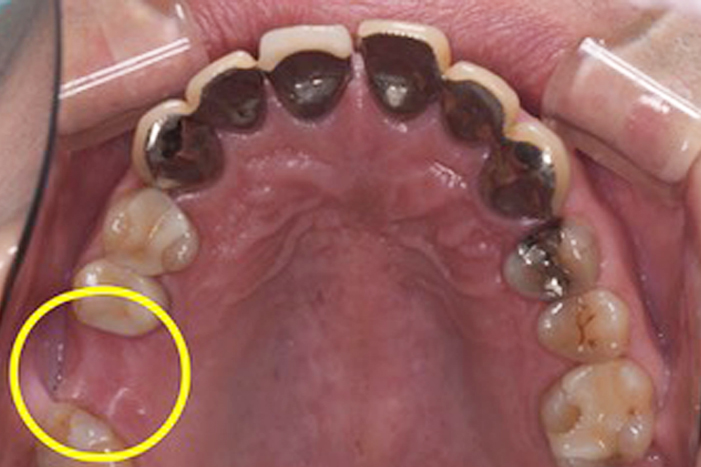

Before

After